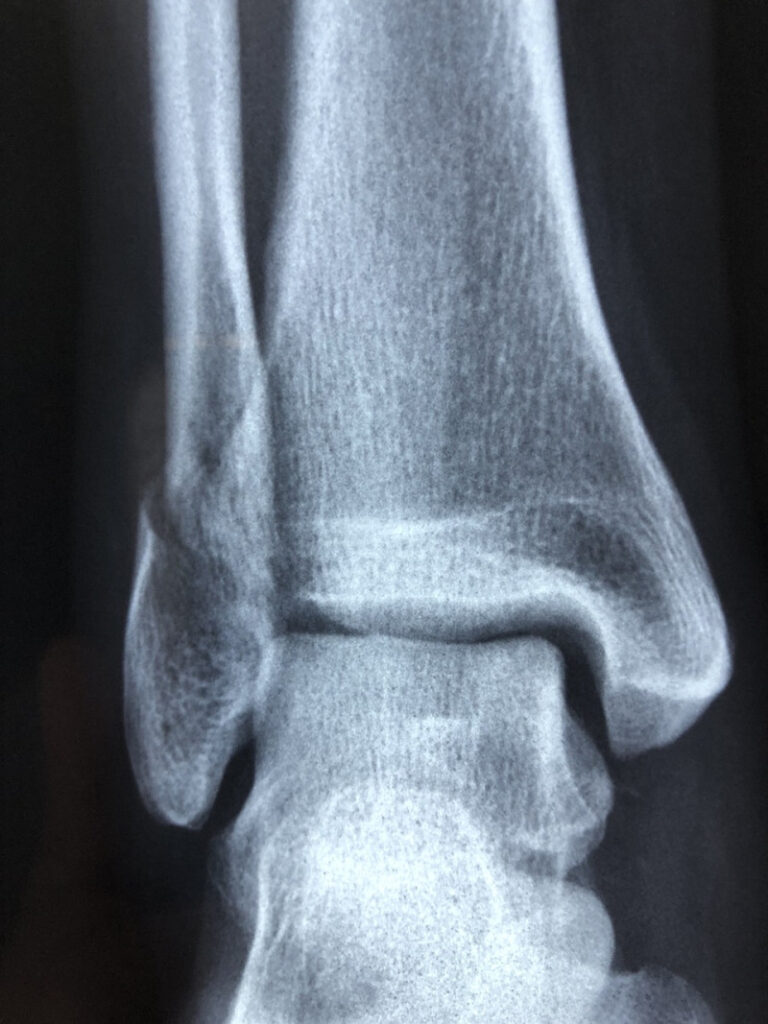

Ankle fractures are common, and in cases where the bones are significantly misaligned or the ankle is unstable, surgery is often required. However, the post- operative management of ankle fractures, particularly the timing of weight-bearing, remains a crucial topic for both patients and healthcare providers. Should you start weight-bearing early, or is it safer to delay?